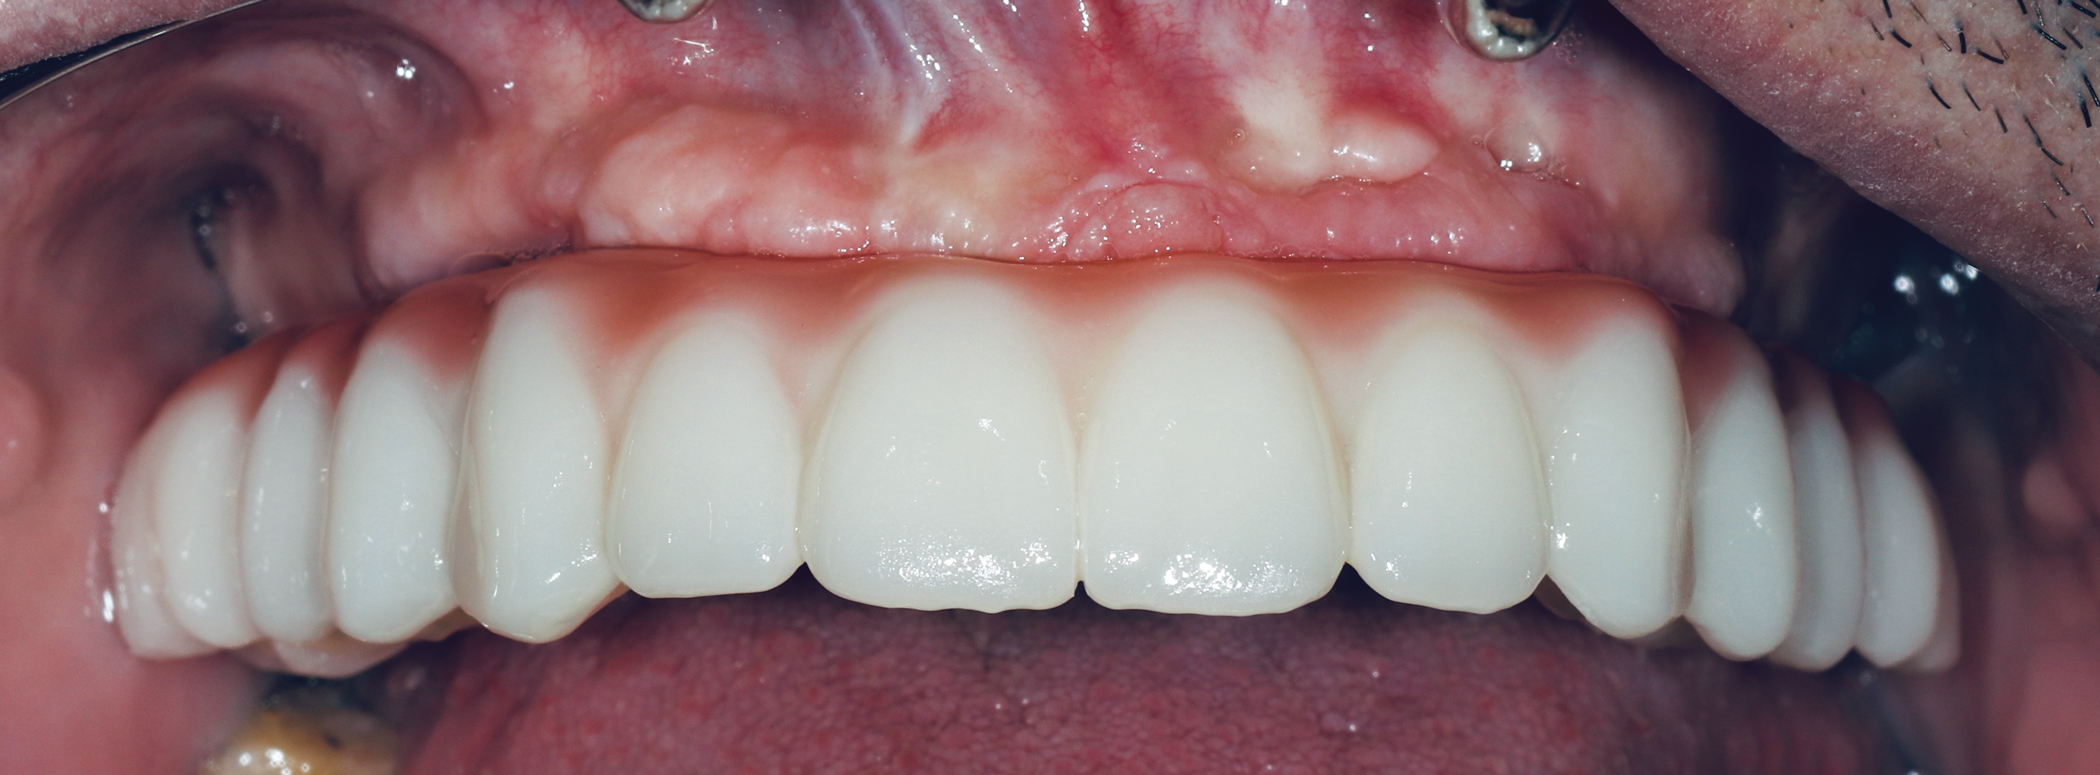

Fig 15. Final zirconia restoration.

Figure 15

The final prosthetic was evaluated using a case check 3D viewer tool (Figure 14). After 2 weeks a final prosthesis was delivered (Figure 15 and Figure 16). At a follow-up visit the patient recorded proper occlusion, excursive movements, and comfort with the new prosthetics.